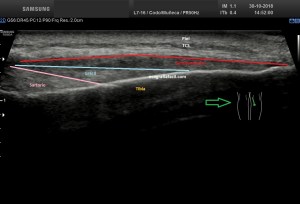

Con la eco pasa igual…cuando queremos estudiar, por ejemplo, el recto anterior del muslo en axial,perfecto…pero en longitudinal, como la imagen 2, se complica porque desde la rótula a la inserción en la cadera, tenemos mucho recorrido. En este caso hacemos lo mismo que cuando hacemos la foto del atardecer…nos ponemos en un extremo, activamos la funciona, recorremos suave y continuamente por la anatomía que queremos fotografiar y ya está…mira la pantalla y no el movimiento de tu mano,como si hicieses la foto, ves la pantalla,pero no como mueves el teléfono.

Es muy útil para lesiones que han crecido mucho y no podemos conjugar en una sola imagen, por ejemplo, un lipoma, cuando superan la medida de la huella de la sonda no son medibles, hay que usar «panoramic view», y como este caso, otros muchos.

Técnicamente es lo mismo, ambos dispositivos hacen una suma de imágenes que se plasman en un resultado final estupendo. Toda la escena más pequeña, pero más alargada que te da percepción de toda la magnitud de aquello que pretendes estudiar, te quita algo de detalle, pero te sirve para medir perfectamente y además puedes incrementar y mover la imagen con tu track ball…